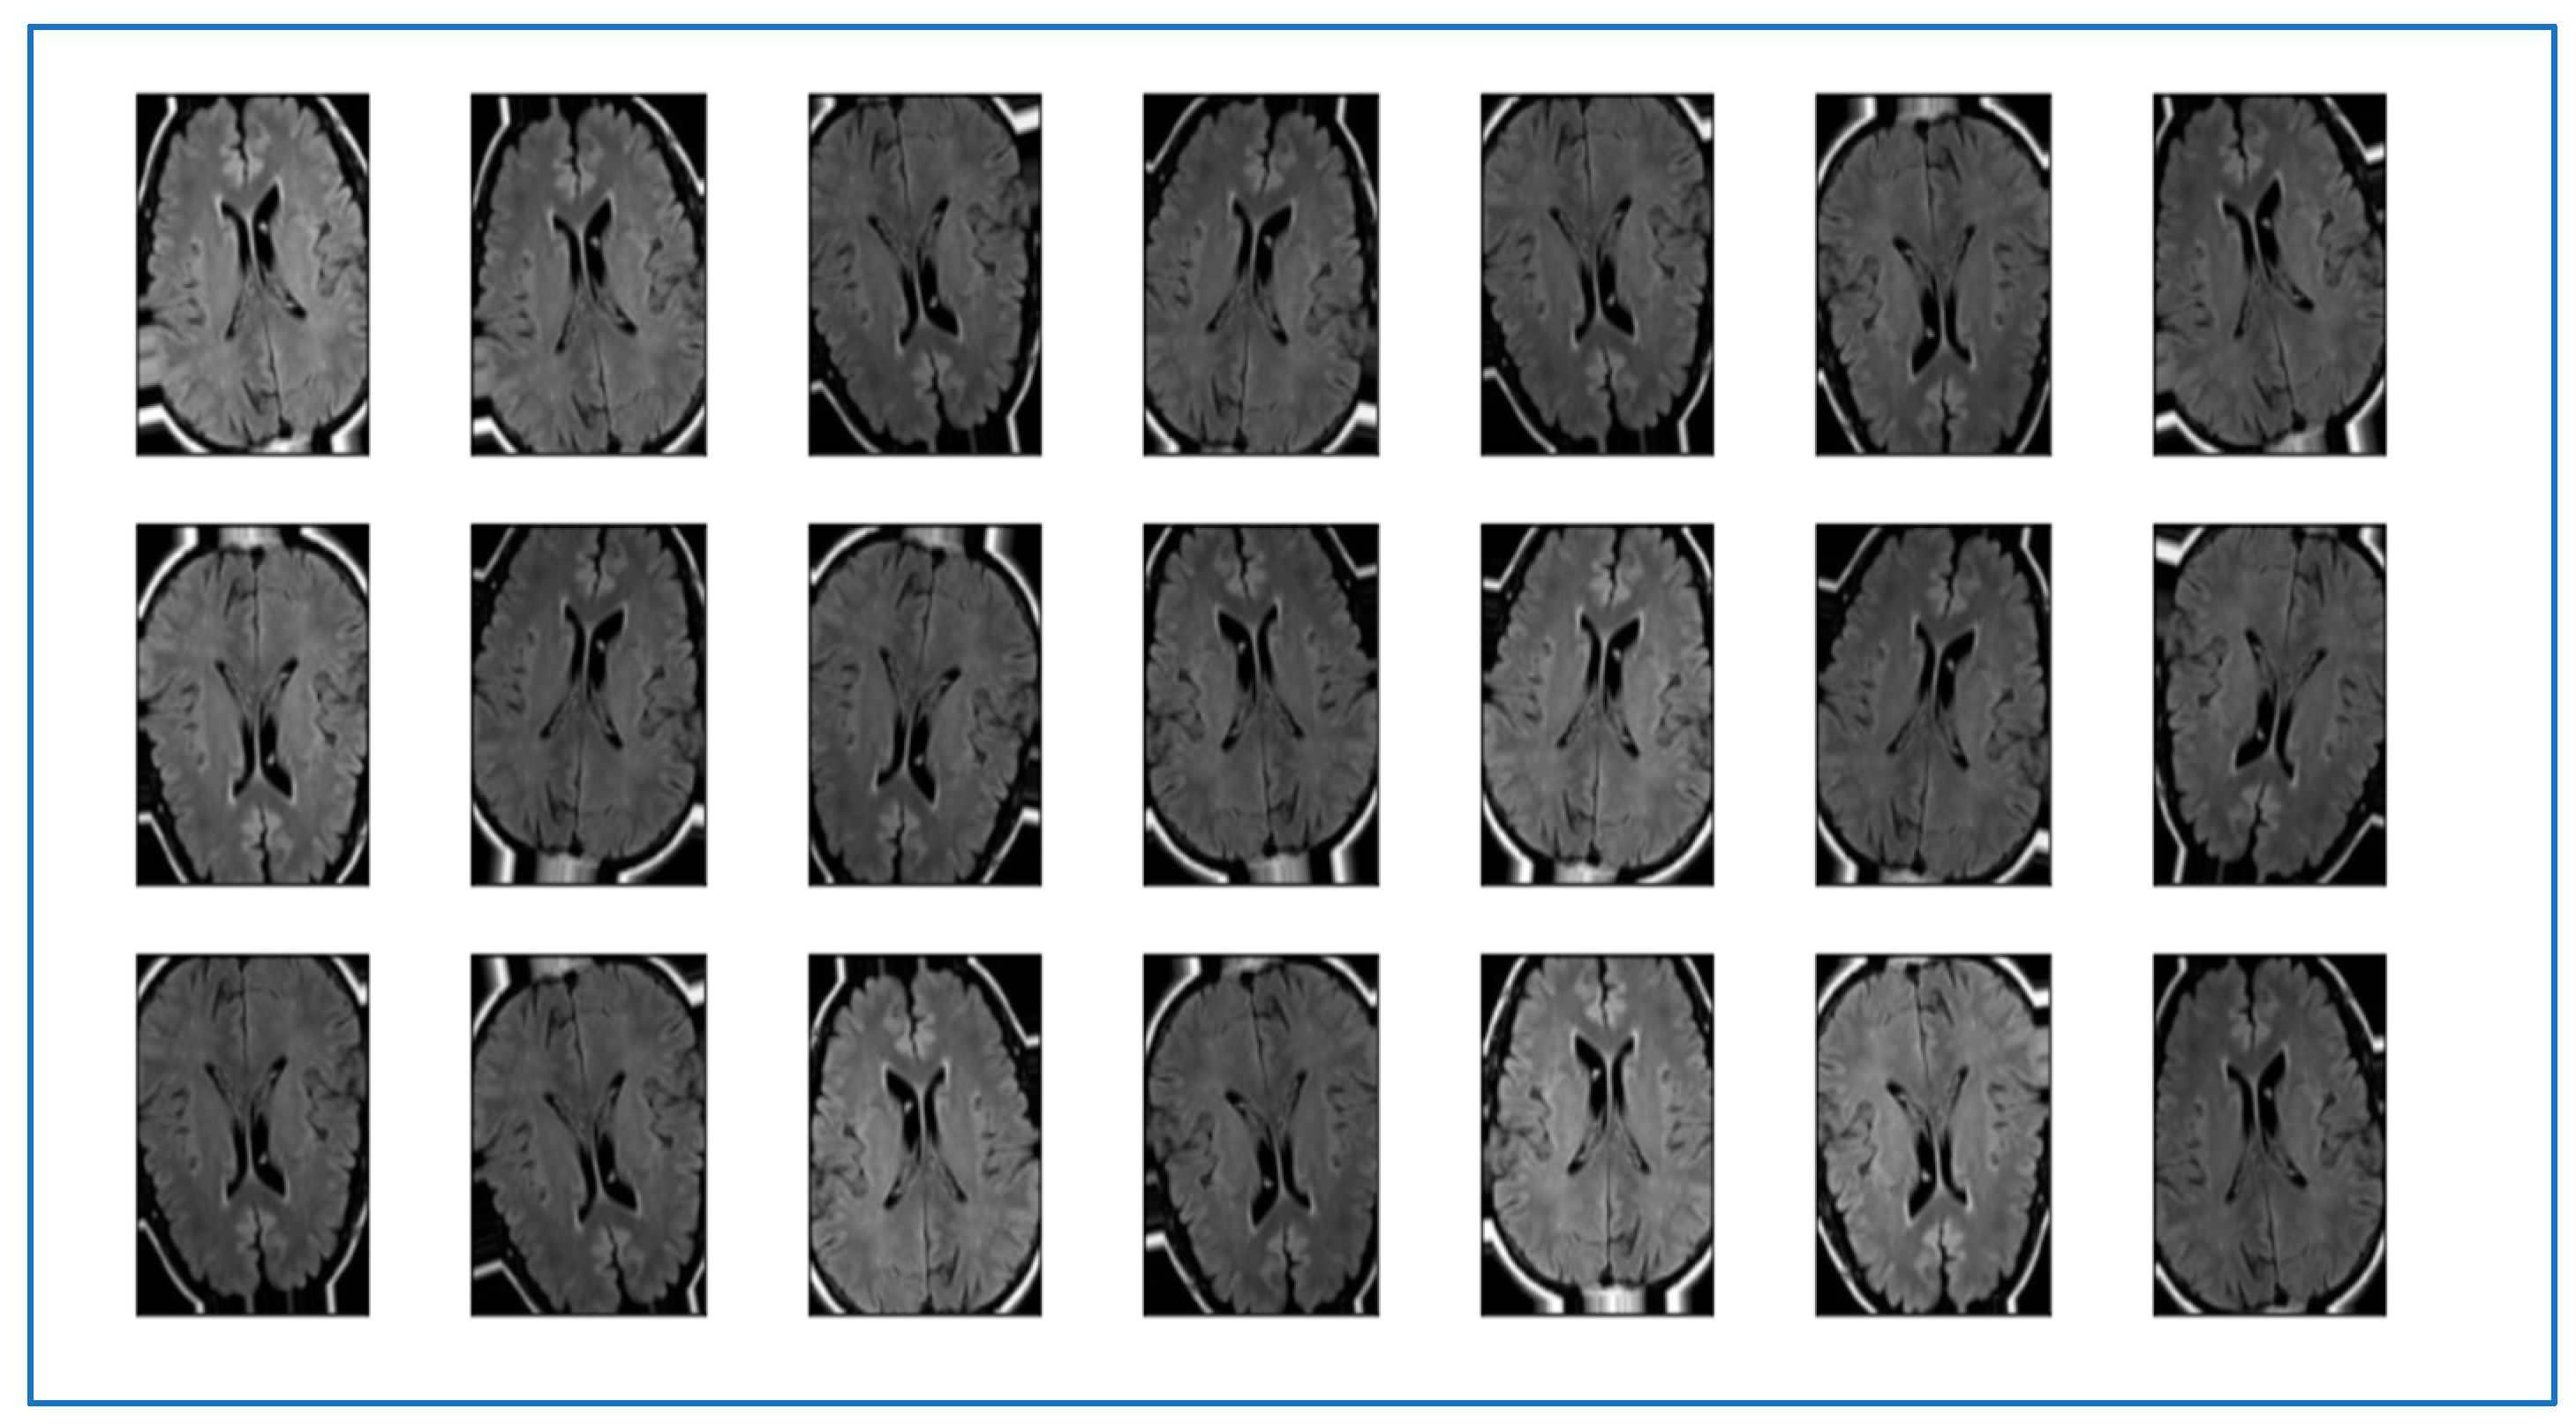

3.1.2. Data Preprocessing

- CLAHE (Construct limited histogram equalization)

- Morphological analysis

3.1.3. Data Segmentation

- Resizing Images

- Data Augmentation